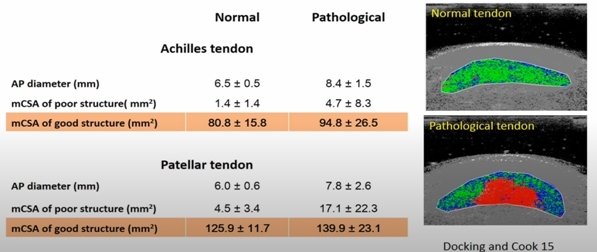

6. Патологичното сухожилие има по-добра структура от нормалното сухожилие(Docking et al. 2015). Това означава, че можем да натоварим тези сухожилия, защото разполагаме с много добра тъкан. Не са необходими никакви терапии за патологията на сухожилията, тъй като така или иначе не можем да променим структурата на патологичната част. Поради тази причина Докинг и колегите му измислят цитата "Лекувайте поничката, а не дупката" - с други думи, съсредоточете се върху здравата структура, а не върху патологичната част.

Патологичното сухожилие има по-добра структура от нормалното сухожилие (Docking et al. 2015)